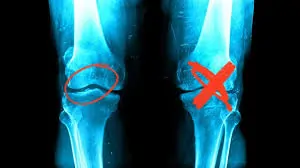

૪. ઘૂંટણના ઘસારાને હરાવી ફરી યાત્રા કરનાર: શ્રી કાંતિલાલ

સમસ્યા: ૭૦ વર્ષના કાંતિલાલને ઘૂંટણમાં ત્રીજા સ્ટેજનો ઘસારો હતો. તેમને ચાલવામાં કટક-કટક અવાજ આવતો અને તેઓ ઘરની બહાર નીકળતા ડરતા હતા.

સારવાર: સમર્પણ ક્લિનિકમાં અમે તેમને ‘ગેઈટ ટ્રેનિંગ’ (ચાલવાની તાલીમ) અને ઘૂંટણની આસપાસના સ્નાયુઓને મજબૂત કરવાની કસરતો કરાવી. સાથે જ હાઈડ્રોથેરાપીની ટિપ્સ આપી. પરિણામ: કાંતિલાલ તાજેતરમાં જ ચારધામની યાત્રા સફળતાપૂર્વક કરીને આવ્યા છે. તેમણે અમને આશીર્વાદ આપતા કહ્યું કે, “ફિઝિયોથેરાપીએ મારા ઘરડા પગમાં નવું જોમ પૂર્યું છે.”